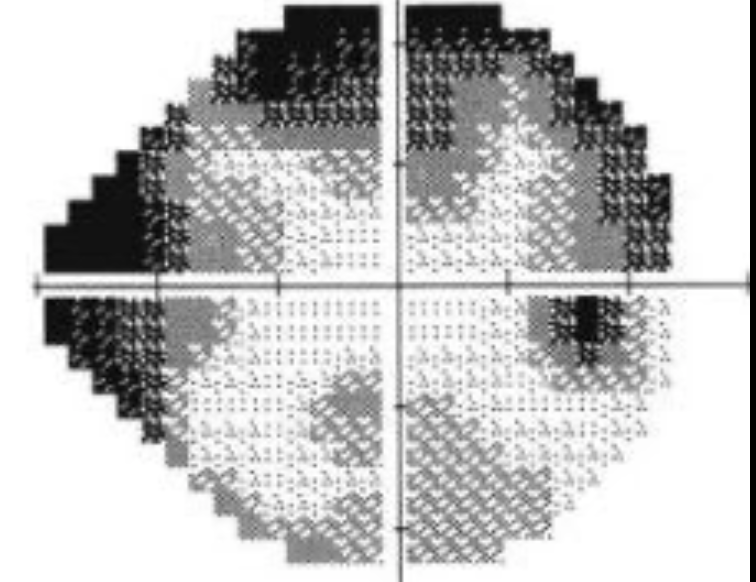

Como apresenta-se no campo visual o excesso de falso negativos?

Trevo de 4 folhas

Quais pacientes estão propensos a um maior percentual de falso negativos?

Pacientes desatentos e simuladores

Pacientes com glaucoma - há variabilidade em aulas previamente lesadas